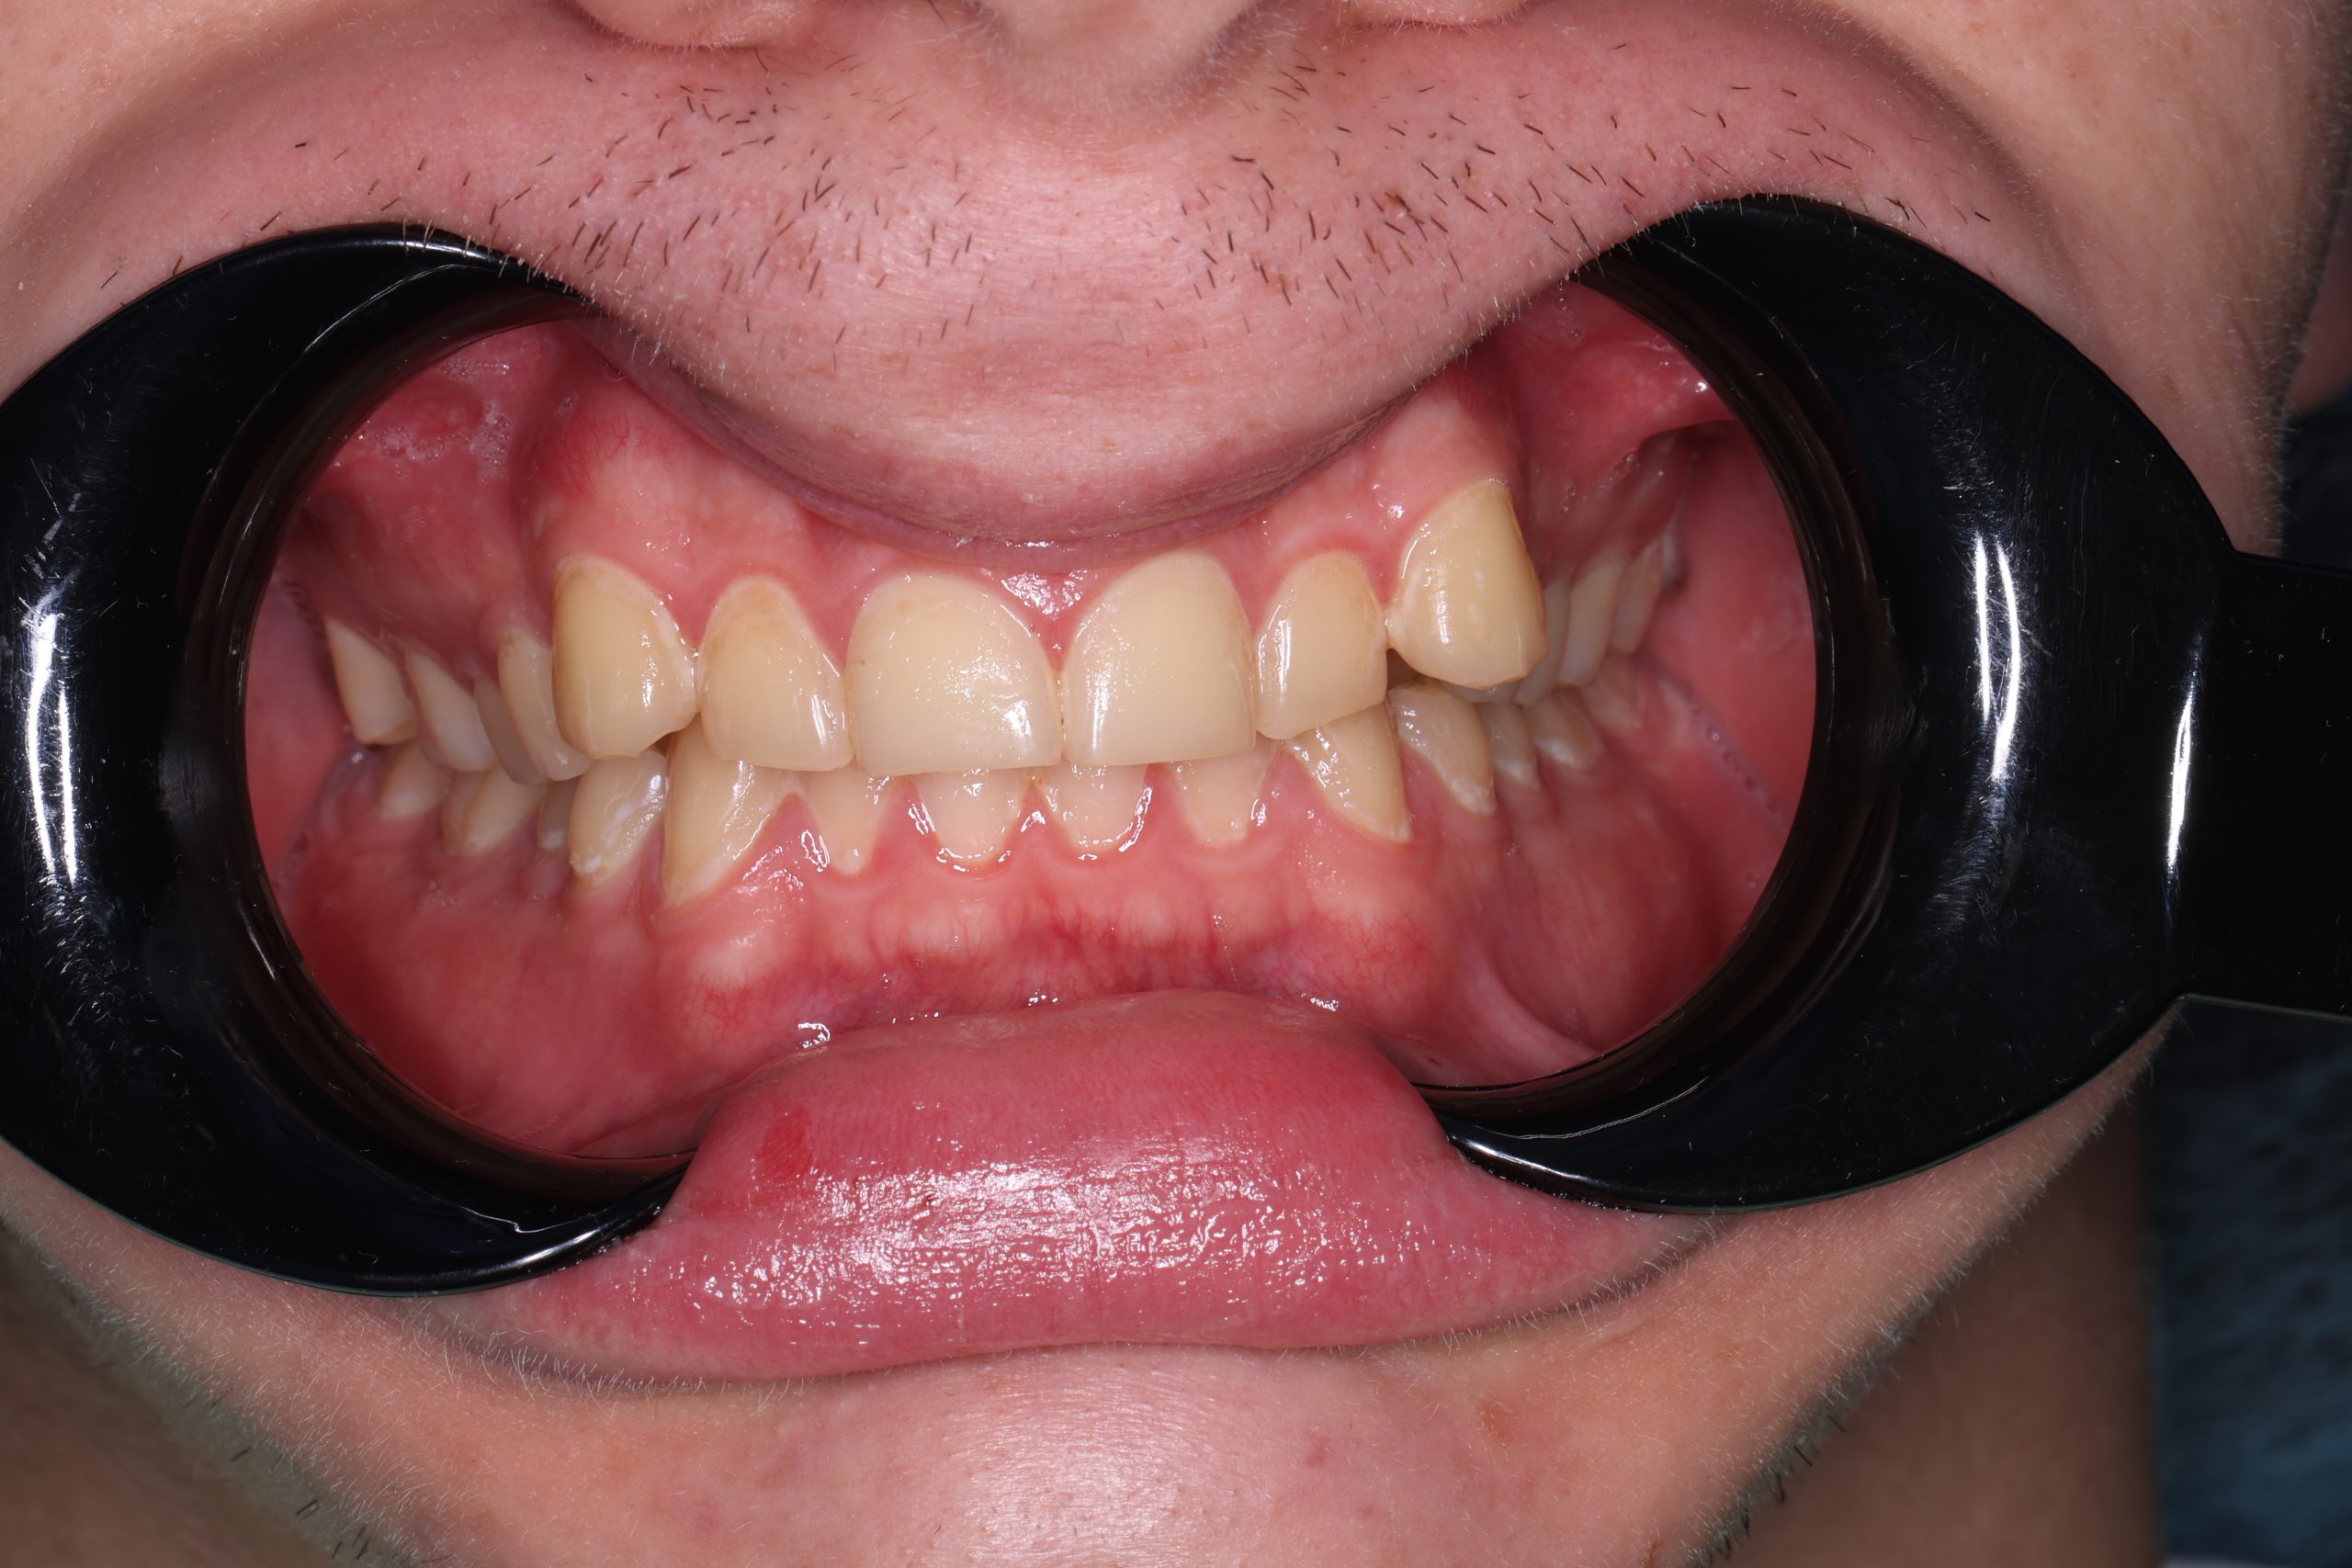

Your natural tooth is part of a living system. It transfers chewing forces correctly, supports surrounding bone and gums, and keeps neighbouring teeth aligned. Losing it may lead to a chain of further treatments — implants, bridges, or shifting teeth that change your bite. Preserving what nature gave you is almost always the wiser, more conservative choice.

Signs You Might Need Root Canal Therapy

- Persistent sensitivity to hot or cold

- Pain when chewing or releasing the bite

- Throbbing pain at night

- A small bump on the gum near the tooth

- Darkening after trauma

- Recurrence of pain in a tooth that was previously treated